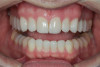

(10.) Postoperative smile photograph.

Figure 10

(11.) Postoperative retracted view.

Figure 11

After the composite veneers were finalized, impressions were taken for a monolithic lithium disilicate crown on tooth No. 12. This was placed during a subsequent appointment, and occlusal equilibration was carried out. The patient returned for final photographs a couple of weeks later (Figure 10 through Figure 14).